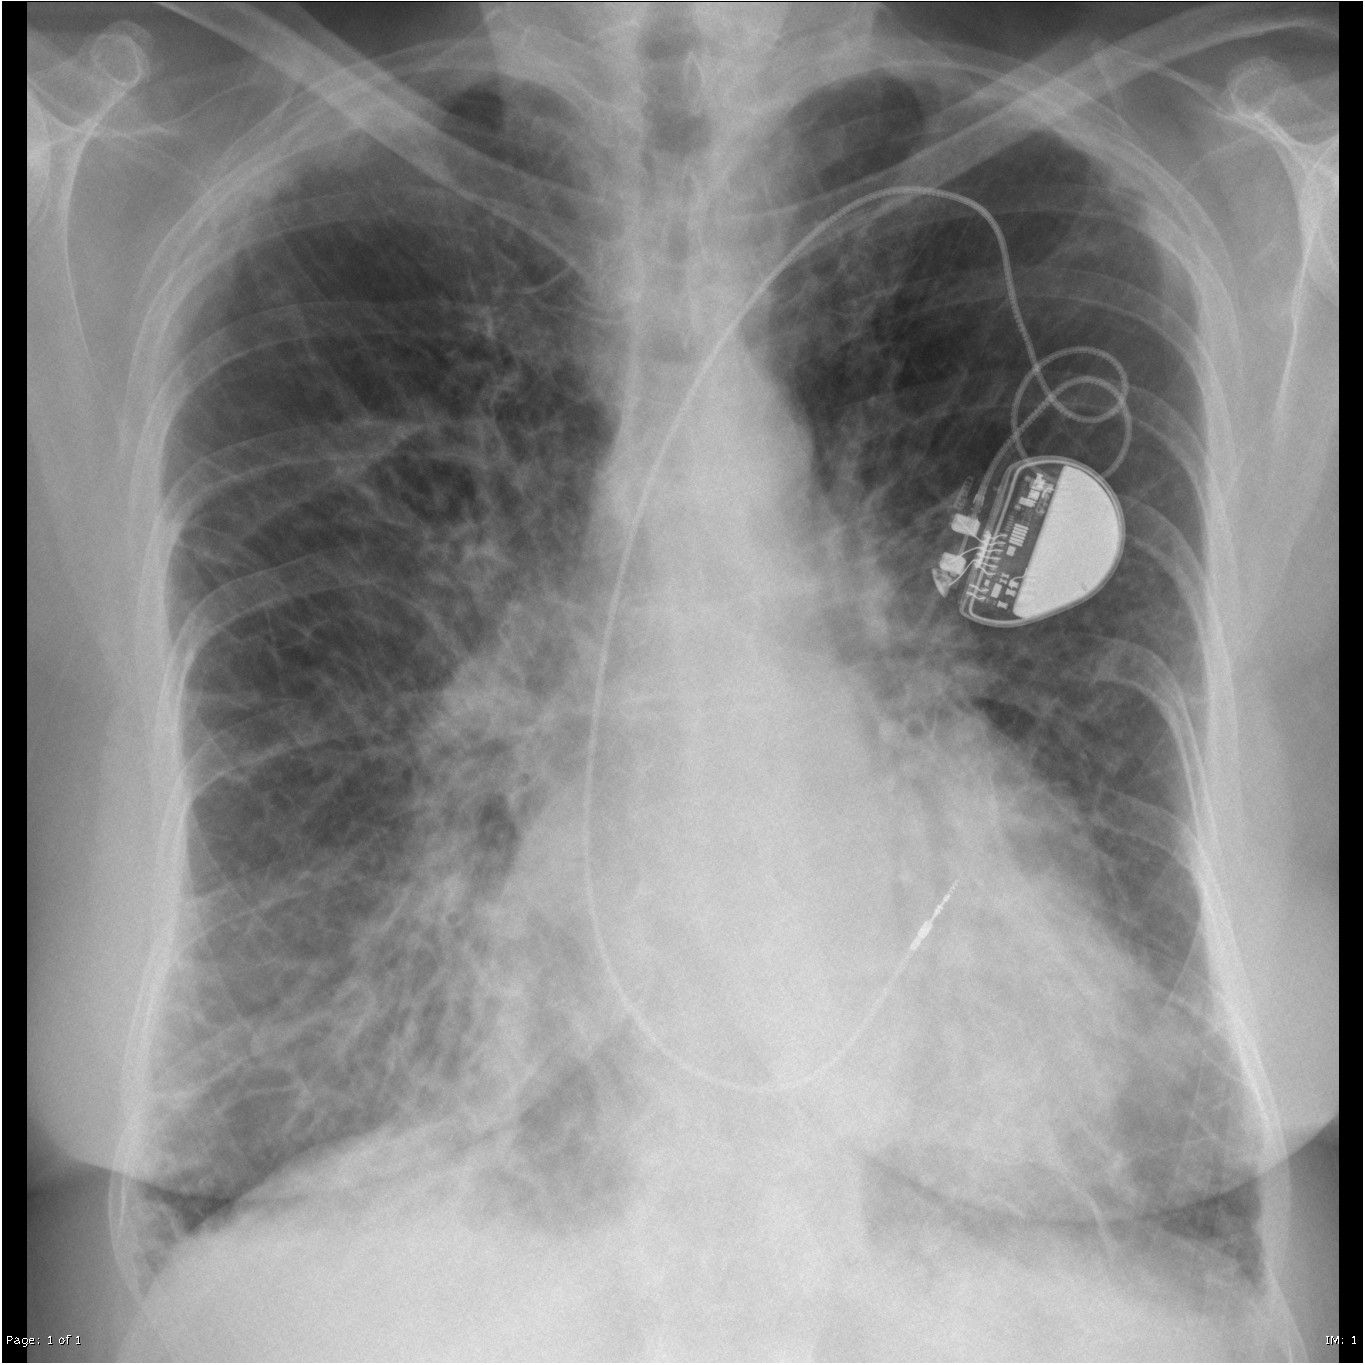

Поражение легких является одним из основных симптомов коронавируса (COVID-19). В данной статье представлены фото рентгеновских снимков, которые позволяют визуально оценить состояние легких при этом заболевании.

Коронавирус пневмония рентген

Рентген легких пневмония коронавирус

На фотографиях рентгеновских снимков видно, как вирус воздействует на легочную ткань. Характерные признаки поражения легких включают пятна, инфильтраты и наличие жидкости внутри легочных альвеол.

Фото рентгеновских снимков помогают врачам и специалистам визуально определить степень поражения легких и принять соответствующие меры лечения и поддержки пациента.